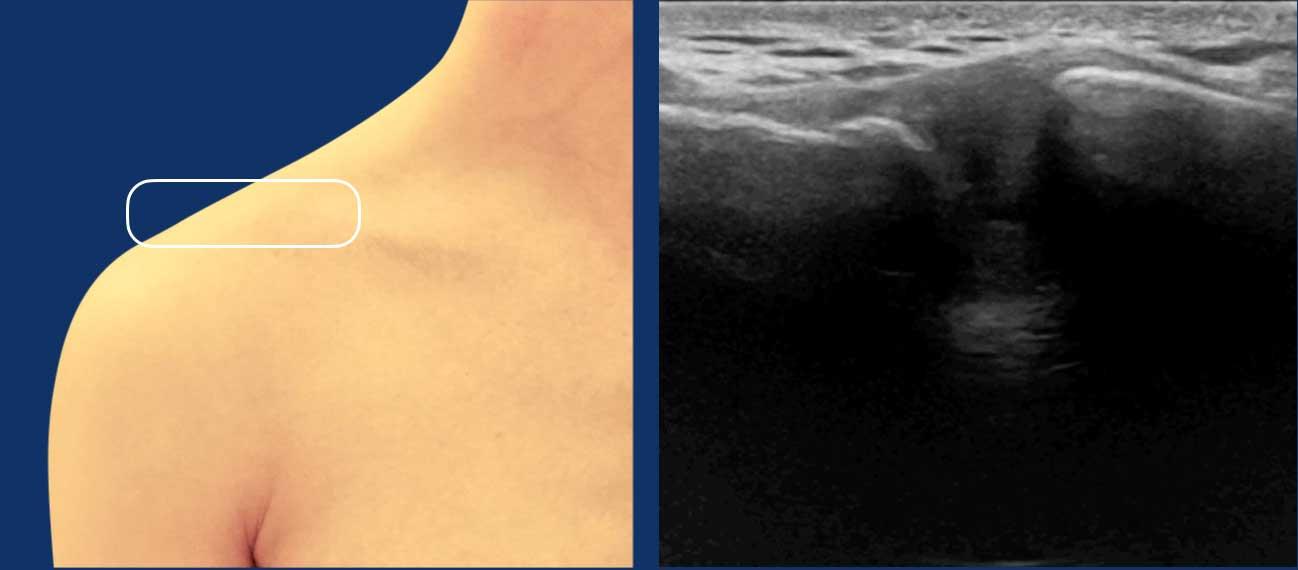

Spinoglenoid notch

Xác định gai xương bả vai như một mốc xương tăng âm.

Di chuyển đầu dò sang bên cho đến khi xác định được khuyết gai-ổ chảo, nằm giữa gai xương bả vai phía ngoài và mỏm ổ chảo.

Thần kinh trên vai xuất hiện dưới dạng cấu trúc hình ống giảm âm với hình thái bó sợi (mũi tên).

Doppler năng lượng có thể hữu ích để theo dõi các mạch máu trên vai nhằm xác định vị trí thần kinh.

Kiểm tra các nang hạch, có thể xuất hiện dưới dạng các cấu trúc giảm âm, chứa dịch, chèn ép thần kinh trên vai.

Các nang này thường liên quan đến rách sụn viền ổ chảo mặt sau trên.